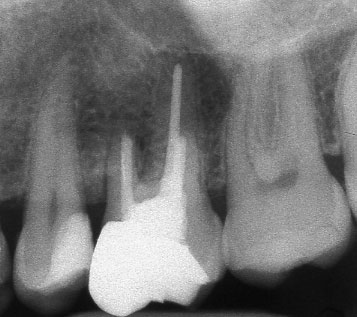

Рентгенографии на добре пролекувани зъби

При добре проведено ендодонтско лечение кореновият канал е запълнен точно до стеснението, разположено на 1 - 1.5 мм. от края на канала - т.нар. физиологично стеснение. Не бива да остава незапълнена част от канала. Много често се получава припресване на канлопълнежното средство извън канал на зъба, в тъканите около корена.